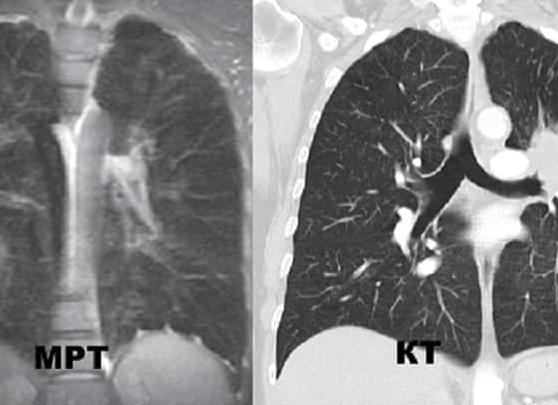

МРТ исследование является одним из самых современных методов изучения организма человека, которое широко используется при диагностике разных патологических состояний головного мозга. Благодаря ей можно увидеть любой орган послойно, а также очень точно оценить состояния структуры мягких тканей. Этот вид томографии является безопасным, качественным и высокоинформативным диагностическим исследованием.